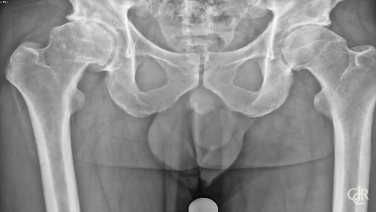

Anterior Advantage MATTA METHOD Acetabulum Cup Insertion - David DeCook MD

Femoroacetabular Impingement Management with Jonathon Salava, MD